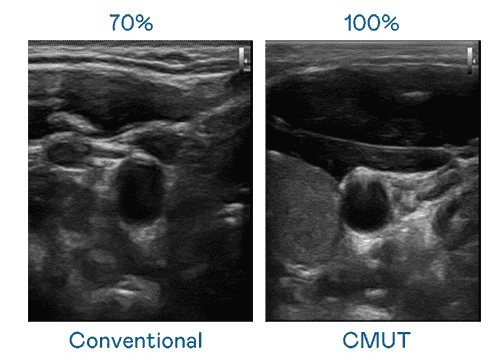

CMUT 技术是一种用电容式微机电元件来产生超音波讯号的技术。。。与传统 PZT 压电式技术相比,,,CMUT 频宽增加 30%,,更宽频的超音波讯号让影像解析度大幅提升,,,,是实现高影像品质医疗超音波扫描、、、促进精准医疗发展的关键技术。。。

大频宽带来超清晰影像

超音波影像的解析度高低,,,,首先取决于探头能发出的讯号频宽。。优游UB8 CMUT 可提供高清晰的超音波讯号,,,,提供高频宽、、、高灵敏度、、、、影像纹理细节更高的超音波影像,,协助医护人员缩短影像判读时间及利用精准的医疗影像进行诊断。。。。